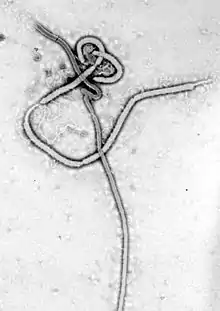

8 August 2014: WHO declared the Ebola outbreak in West Africa (virus pictured), the most widespread so far, an international public health emergency

26 August 1976: First case of Ebola virus, now the Zaire form

8 September 1976: Death of Mabalo Lokela, the first known case of Ebola virus

24 November 2007: Outbreak of new Ebola species, Bundibugyo virus